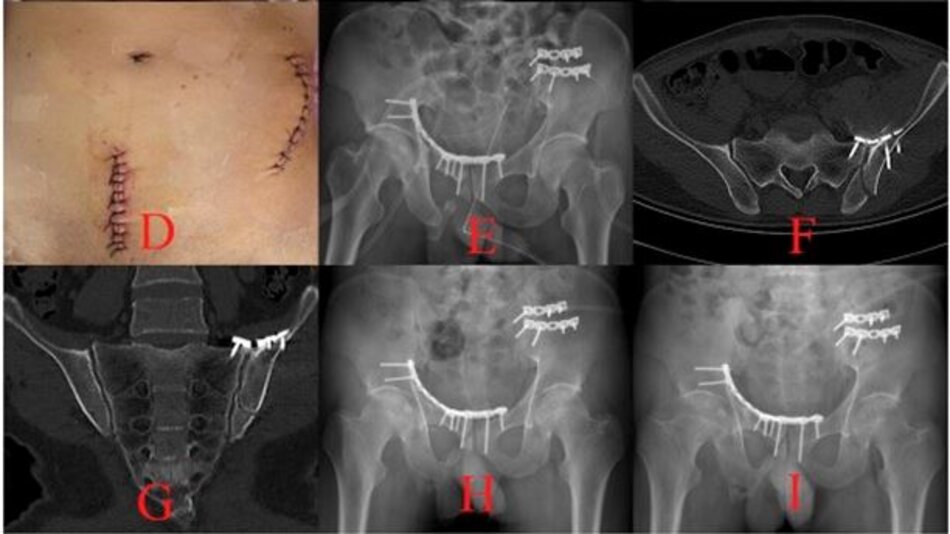

Phẫu thuật Vỡ xương chậu phức tạp

Phẫu thuật đường trước:

Hình ảnh vỡ xương chậu phức tạp

Hình ảnh đường mổ và phim chụp sau mổ đạt kết quả đúng giải phẫu

Phẫu thuật đường sau (Vỡ ổ cối)

X quang trước mổ

X quang sau mổ

Hình ảnh đường mổ